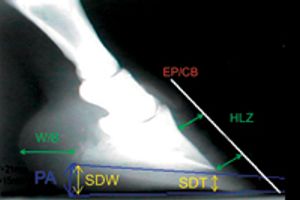

Solving the mathematical needs of a Grade IV laminitic foot.

How to meet the mathematical needs of the higher grades of laminitis.

The mathematical needs of lower grades of laminitis.